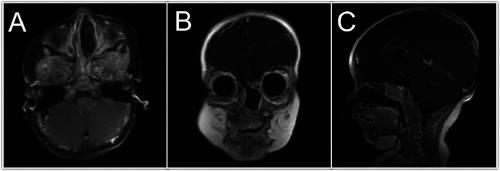

图2 在对比后图像(A)轴向、(B)冠状和(C)矢状中,左鼻肿块没有观察到对比增强